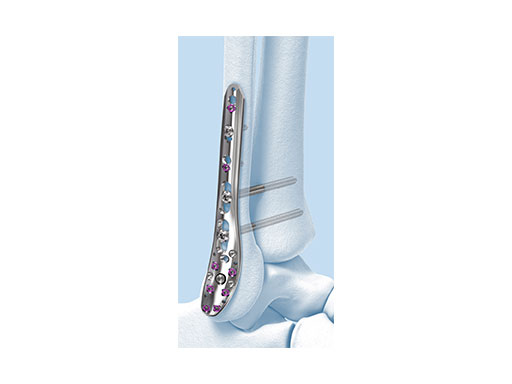

The Variable Angle LCP Ankle Trauma system also comprises a compression and distraction system, which is an important tool for reduction (i.e. bringing a fibula out to length) or compression of a fracture through the plate itself (Fig 9a-d). The forceps allow for final screw fixation after compression or distraction has been achieved.

A 45-year-old patient fell from his horse, receiving a closed bimalleolar fracture/ dislocation (Fig 10). Computed tomorgraphy demonstrated an additional anterolateral avulsion injury and syndesmosis dislocation. Osteosynthesis was conducted with a VA-LCP Lateral Distal Fibula Plate.

Push technique was required to achieve fibular reduction, and the syndesmosis was reduced and clamped with periarticular clamps (Fig 11). Postoperative x-rays at 4 weeks demonstrated good maintenance of reduction (Fig 12).